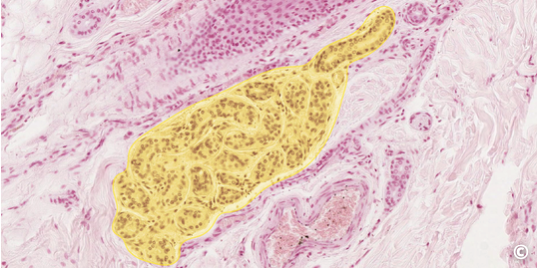

<p>what this</p>

what this

sebaceous gland (branched alveolar/acinar gland)